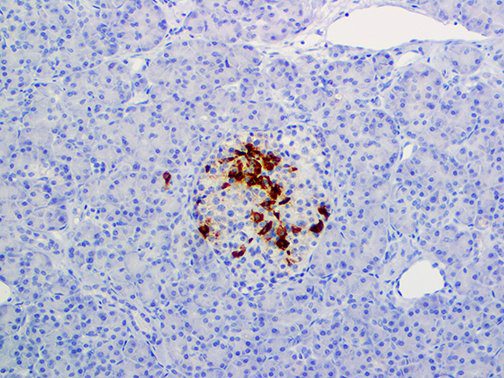

It is the ICU physician who is most likely to witness one of the deadliest manifestations of the abnormal immunological response, the cytokine storm syndrome (CSS). This response is also referred to by some as the cytokine release syndrome (CRS). CSS is characterized by continuous activation and expansion of macrophage and lymphocyte populations, which secrete large amounts of cytokines, causing the cytokine storm. This massive cytokine release is akin to hemophagocytic lymphohistiocytosis (HLH) disease, a syndrome characterized by initial unchecked and persistent activation of cytotoxic T lymphocytes and NK cells.

Clinical and laboratory manifestations of HLH include fever, enlarged liver and/or spleen, neurologic dysfunction, coagulopathy, liver dysfunction, cytopenias (i.e., low levels of erythrocytes, leukocytes, and/or platelets), hypertriglyceridemia, hyperferritinemia, hemophagocytosis, and eventually diminished NK cell activity as the immune system becomes progressively paralyzed. HLH can be familial (primary HLH) or secondary to another disease process (sHLH), such as rheumatic disease, in which it is referred to as macrophage activation syndrome (MAS, characterized by elevated ferritin).